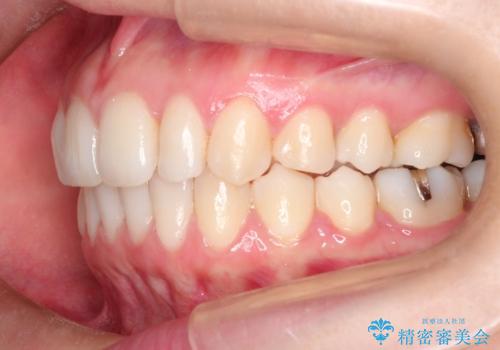

見た目、嚙み合わせ及び、治療期間や施術内容に大変ご満足いただきました。